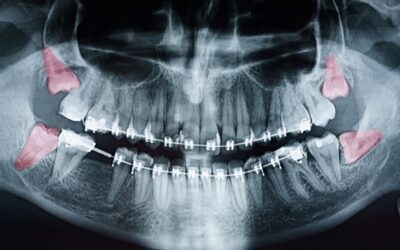

Preciso mesmo extrair o dente do siso? Quando é recomendado?

Quer saber se todas as pessoas devem extrair o dente do siso? Pois saiba que esta é uma das dúvidas mais recorrentes em meus atendimentos. Mas antes de responder diretamente este questionamento falaremos rapidamente sobre o dente...